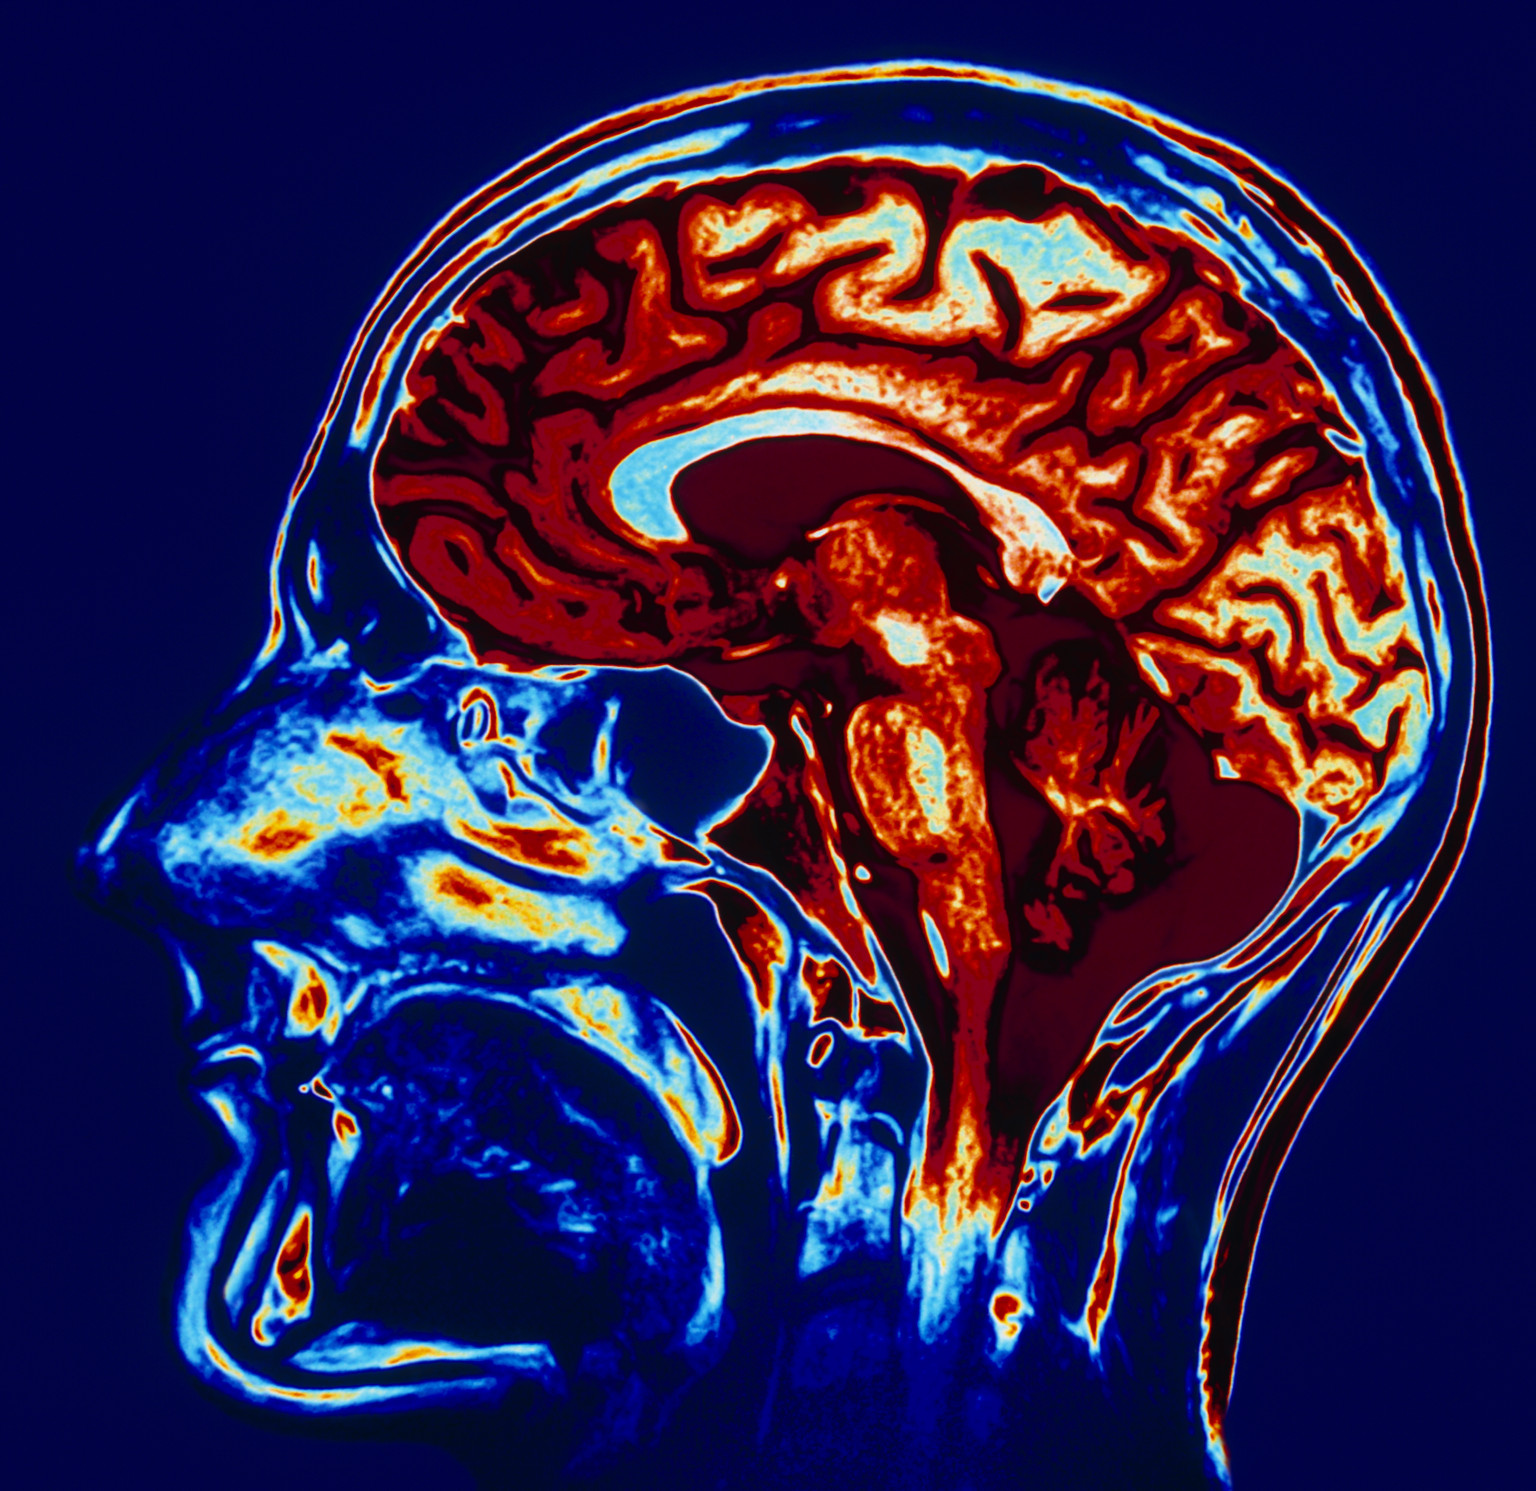

Mri brain scan alzheimer using space imaging human software scans wikipedia identifying esa researchers hypothalamus applications pillars medical wiki thalamus. Brain scans scan cte concussion athletes football may concussions mainichi nfl players reveal living damage after shows april former boston. Brain mri scan coloured sagittal geoff tompkinson se photograph like numbers brains drips vitamin peddling doctors pointless stressed when look